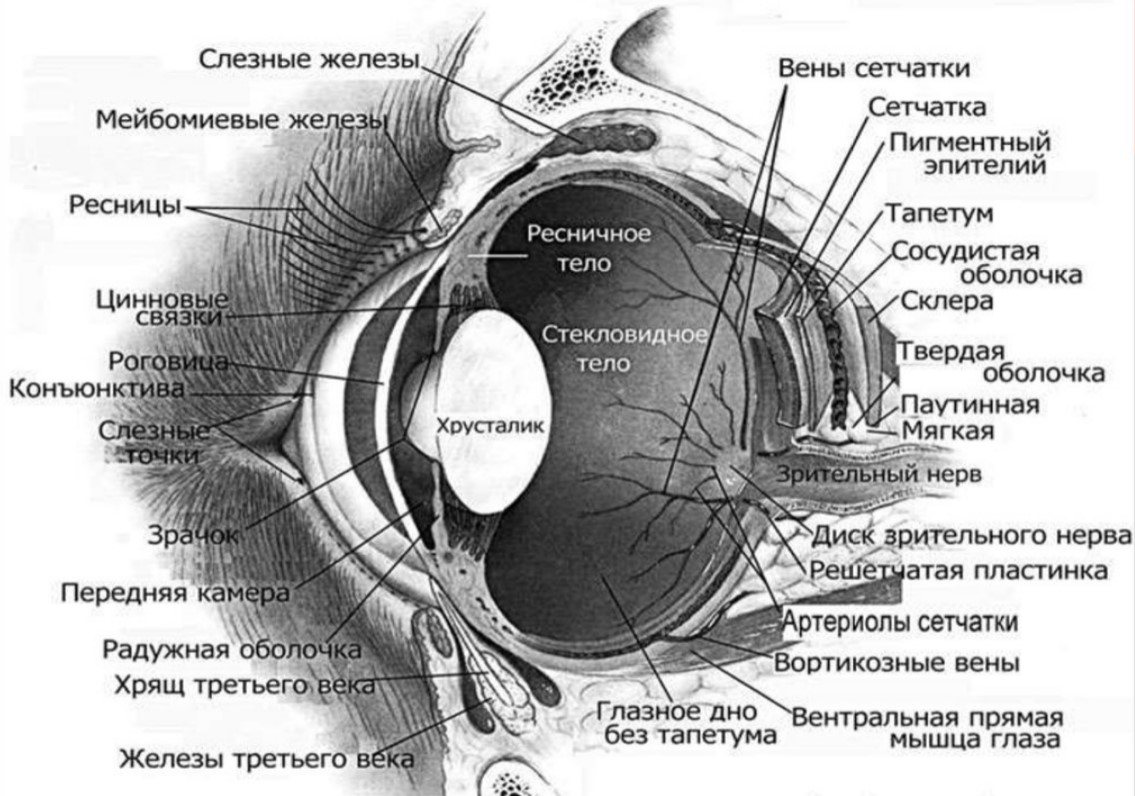

КТ-графики и изображение строения глаза